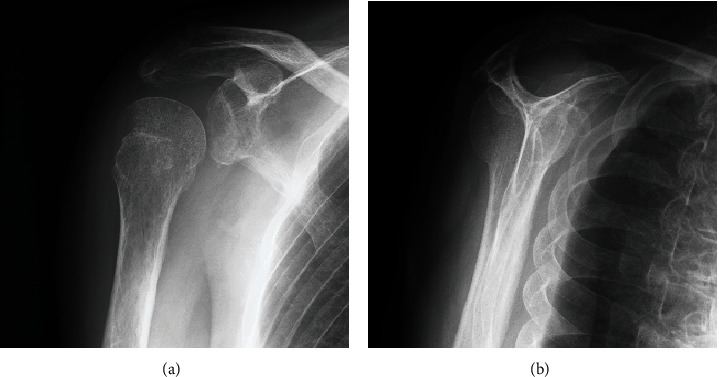

Posterior dislocation of the shoulder joint is a rare condition. It is often misdiagnosed owing to a lack of evident clinical features compared with anterior shoulder dislocation, and inappropriate radiological examination. We present a case of chronic posterior fracture dislocation treated with greater tuberosity osteotomy. A 66-year-old man was injured in a fall while carrying a drone. He was referred to our hospital following 3 months of conservative treatment at a nearby clinic, without reduction of the posterior dislocation. Physical examination revealed a prominent reduction in shoulder joint range of motion and shoulder pain. Radiological examination revealed posterior shoulder dislocation associated with greater tuberosity malunion and a small bone fracture of the posterior portion of the glenoid. Open reduction and internal fixation, including greater tuberosity osteotomy, were performed. Although subluxation of the posterior dislocation persisted postoperatively, the humeral head gradually returned to its centric shoulder joint position owing to rotator cuff force coupling. At 24-month follow-up, the patient showed excellent shoulder results.